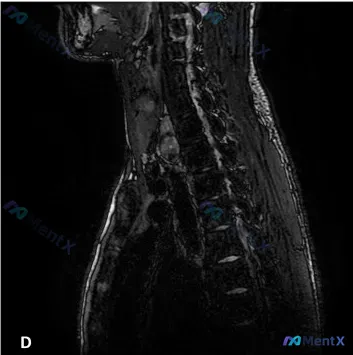

整理到一张颈胸段脊柱MRI-T2矢状位的影像资料,先把核心影像表现列出来,大家第一眼会怎么考虑?

- 椎间盘与椎间隙:多节段颈椎及上胸椎椎间盘低信号(“黑盘”),椎间隙普遍变窄,下颈椎(C5-C7左右)更明显;多节段后缘局限性突起,压向椎管。

- 椎体与终板:椎体骨髓信号不均,多个椎体前后缘骨赘形成;部分终板呈高信号(有Modic改变迹象);未见明确急性骨折或显著破坏性病灶。

- 脊髓与椎管:脊髓前方脑脊液间隙因椎间盘后突、骨赘增生明显变窄,呈“刀切样”;受压最重的C5-C6/C6-C7水平脊髓内可见片状异常高信号;后纵韧带区域信号复杂,不排除骨化/钙化可能,合并黄韧带肥厚可能,形成前后压迫。

- 脊柱序列:颈椎生理前凸消失变直,序列基本连续,无明显滑脱。